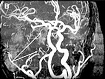

МРТ – это компьютерное исследование, тоже скрининговый метод, он дороже УЗДГ почти в 4 раза. Показанием для проведения этого метода исследования служат подозрения на патологические изменения в структурах мозга, в том числе и в сосудистом русле, находящемся внутри черепной коробки (рис. 3).

Рис. 3. МРТ-реконструкция брахиоцефальных артерий.

(Магнитно-резонансная ангиография артерий). Белыми стрелками показаны: сужение (стеноз) правой внутренней сонной артерии (А); стеноз левой сонной артерии и закупорка (окклюзия) правой (В); окклюзия левой внутренней сонной артерии (В); стеноз правой позвоночной артерии (Г); извитость правой и левой сонных артерий (Д)).

Рис. 3. МРТ-реконструкция брахиоцефальных артерий.(Магнитно-резонансная ангиография артерий). Белыми стрелками показаны: сужение (стеноз) правой внутренней сонной артерии (А); стеноз левой сонной артерии и закупорка (окклюзия) правой (В); окклюзия левой внутренней сонной артерии (В); стеноз правой позвоночной артерии (Г); извитость правой и левой сонных артерий (Д)).